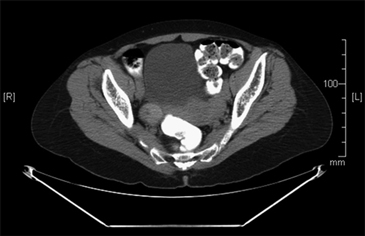

Una paciente de 61 años consultó al servicio de ginecología por un cuadro de hemorragia uterina anormal, para este momento la paciente no refería ningún otro síntoma. Dentro de los estudios solicitados la ecografía transvaginal reportó una imagen quística de 3 cm con múltiples septos y papilas en su interior en el ovario derecho que posteriormente fue caracterizado mediante una tomografía de abdomen y pelvis (Figura 1). Cuatro meses después de haber consultado, y con la sospecha de un carcinoma de ovario fue llevada a cirugía donde se realizó resección de ambos ovarios y útero y no se encontró compromiso macroscópico más allá del ovario; no presentó complicaciones asociadas al procedimiento. En la evaluación de patología describen en el ovario derecho un foco de 0,5 x 0,6 cm de un carcinoma papilar variedad folicular de tiroides en un struma ovarii (Figura 2).

Figura 1. Tomografía de abdomen y pelvis. Ovario derecho de 29 x 30 cm ligeramente aumentado de tamaño de aspecto heterogéneo.